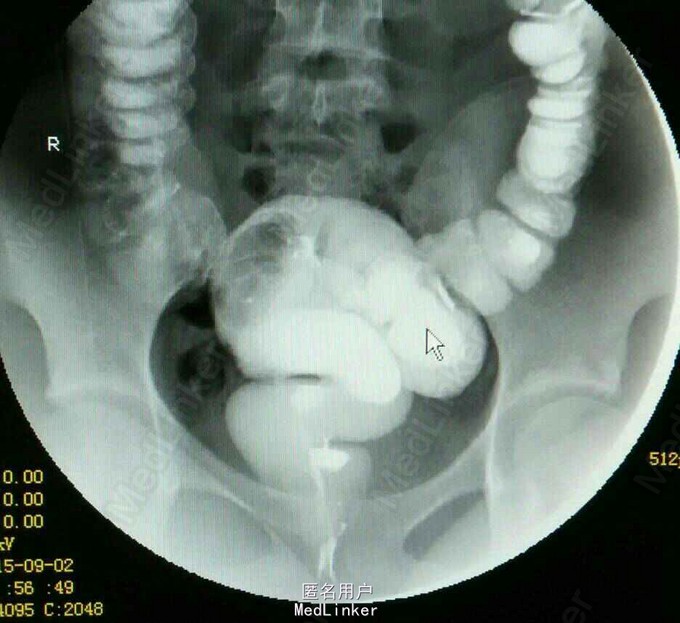

患儿女,10岁,因反复便秘5年余入院。伴腹痛、呕吐。

查体:腹胀,无压痛反跳痛。脑膜刺激征阴性。辅查:消化道造影提示巨结肠。测肛门压力增高

诊断:便秘查因:巨结肠? 处理:予禁食,胃肠减压处理。联系病理活检。入院5天后患儿仍有便秘。转小儿外科拟行造瘘手术。

讨论:巨结肠多为先天性,该患儿较大,巨结肠为后天性可能性较大。便秘接诊时还是应该警惕器质性病变。